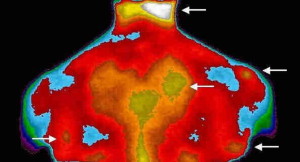

“La fibromialgia – spiega Piercarlo Sarzi Puttini, Direttore U.O. Complessa di Reumatologia, A.O. Polo Universitario “L. Sacco” – non è una sindrome depressiva o immaginaria come molti medici ancora credono, ma una malattia vera, che interessa i tessuti molli (e non le articolazioni) e si presenta con dolori muscolari, affaticamento cronico, ipersensibilità al dolore proveniente anche da stimoli cutanei innocui, mal di testa, disturbi del sonno. Questa alterazione periferica e centrale dei meccanismi del dolore fa sì che ogni stimolo, anche quello più naturale e fisiologico – dallo stare in piedi ai i rapporti sessuali – risulti doloroso. E il dolore è cronico, tale da comprometterne la vita”.

Una accurata e attenta anamnesi insieme all’esame dei ‘tender points’ (punti dolenti muscolari) dovrebbe, invece, essere sufficiente al medico per capire immediatamente di cosa si tratta. La cura – continua Sarzi Puttini – consiste nell’utilizzo di farmaci per alzare la soglia del dolore (anticonvulsionanti) o che lo modulino (antidepressivi). Possono essere utili anche coadiuvanti come i sedativi o gli oppiacei come il tramadolo, che si è rivelato efficace in alcuni casi. Ma l’approccio deve sempre essere multidisciplinare. Accanto alla terapia farmacologia deve esserci una riabilitazione fisica graduale per aumentare la resistenza e una psicoterapia cognitivo-comportamentale. Spesso, infatti, i fibromialgici sono persone con seri problemi di traumi affettivi che devono essere approfonditi”.